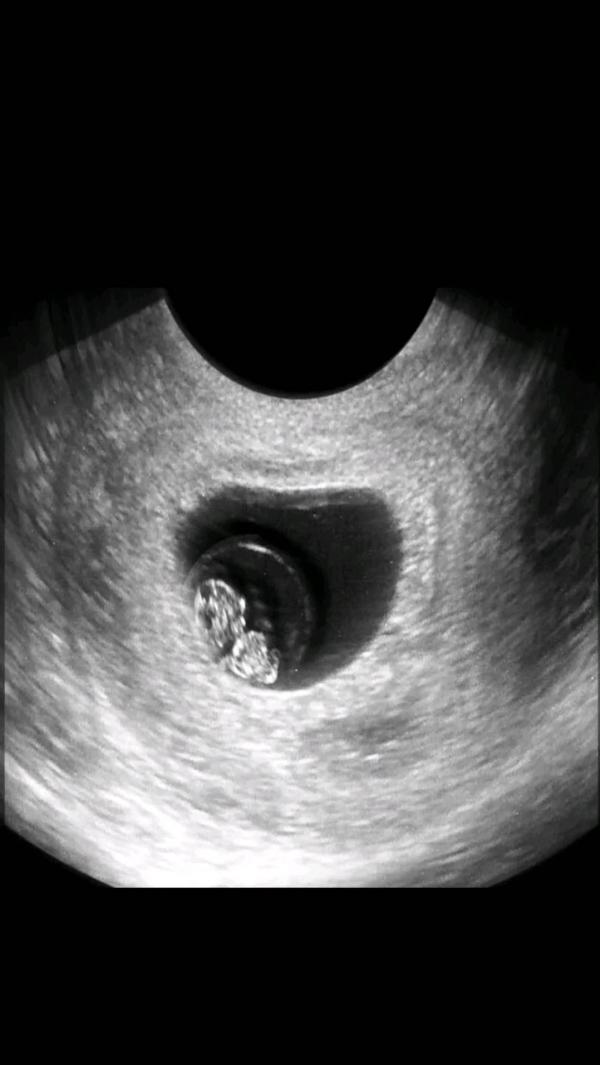

Наше счастье 😍😍

Мы тебя очень любим 😘😘

Ждем безумно 🥰

Какой срок ?

Почти 9 недель

Какой сладкий малыш😍 как мне на первом узи сказали- у вас паразитик 🤣